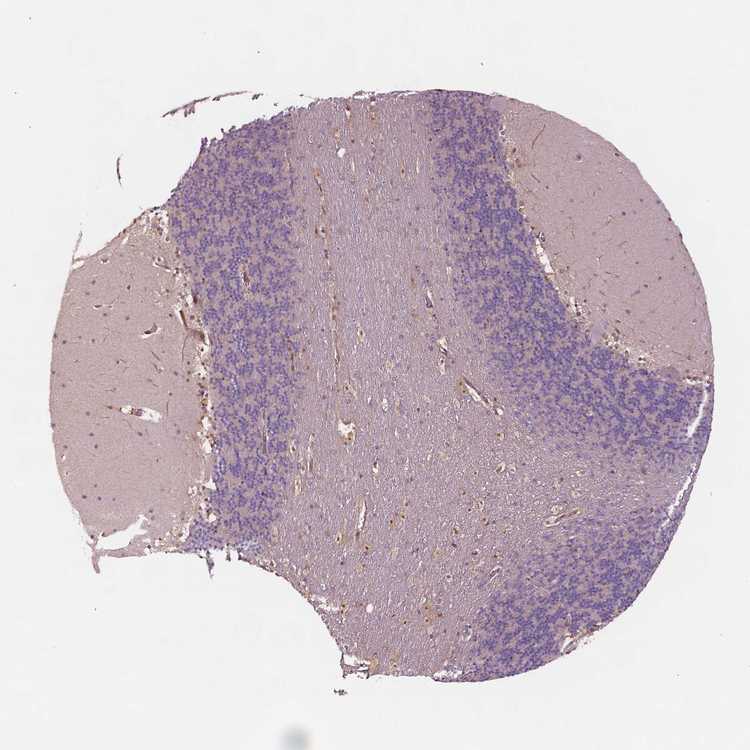

CEREBELLUM - Antibody stainingi

Antibody staining in the annotated cell types in the current human tissue is reported as not detected, low, medium, or high, based on conventional immunohistochemistry profiling in selected tissues. This score is based on the combination of the staining intensity and fraction of stained cells.

Each image is clickable and will lead to virtual microscopy that enables deeper exploration of all samples and also displays staining intensity scores, fraction scores and subcellular localization as well as patient and tissue information for each sample.

Antibody HPA001671Antibody HPA058603Antibody CAB003859Antibody CAB068241Antibody CAB068242

Purkinje cells Not detectedNot detectedMediumNot detected-

Cells in granular layer Not detectedNot detectedNot detectedNot detected-

Cells in molecular layer Not detectedNot detectedNot detectedNot detected-